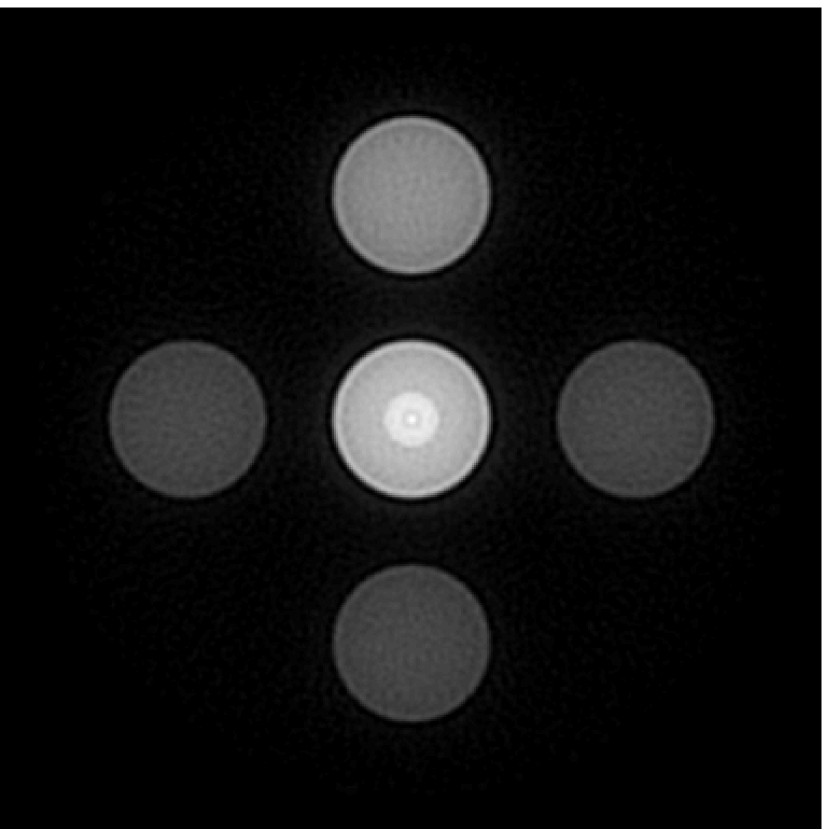

V-B Images reconstructed from noisy data

V-B1 Mitigation of artifacts and distortions caused by an inaccurate EIR

Figure 7(a) reveals that use of the inaccurate EIR in the conventional iterative method created strong artifacts and distortions. Figures 7(b) confirms that the artifacts and distortions were significantly mitigated when the VP method was employed. Image profiles for both cases are shown in Figures 7(c). The overall accuracy of the recovered EIR, shown in Figure 7(d) and 7(e), was improved, but it contained spurious oscillations.

V-B2 Continuous dependency on regularization parameters

Images reconstructed by use of the VP algorithm with different values of the regularization parameter values are shown in Figure 8. The recovered EIRs and their corresponding Fourier spectra are shown in Figures 9 and 10, respectively. The RMSE values are computed and displayed together with the corresponding images. As expected, the images reconstructed with smaller values of contain higher noise levels, while images using larger possess a reduced noise level. However, larger values of also caused artifacts in the reconstructed images. The same observation can be made for the effect of the regularization parameter on the recovered EIR. One also observes that the reconstructed images and EIRs depend continuously on the regularization parameters and , i.e. small changes in the regularization parameters cause minor changes in the reconstructed images and EIRs.